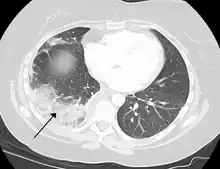

Infarction of the lung due to a pulmonary embolism